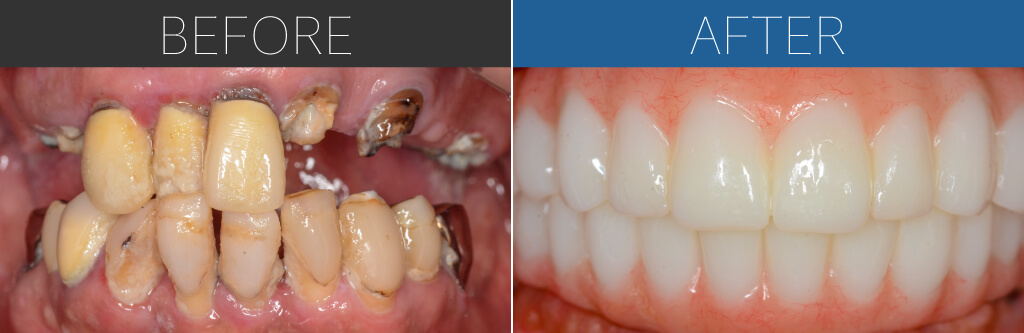

– Upper:All-on-4 + Zygoma

– Lower:All-on-4

Age:60s

| 治療内容 | 差し歯が合わなくなってきて、歯茎に痛みを感じて来院。重度歯周病のため、上顎は通常の埋入が難しくザイゴマインプラント。下顎は基本的な4本埋入によるオールオン4。上下ともに即時荷重により手術当日に仮歯を固定。 |